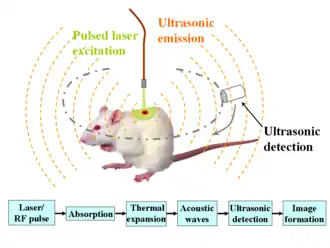

Photoacoustic microscopy is an imaging method based on the photoacoustic effect and is a subset of photoacoustic tomography. Photoacoustic microscopy takes advantage of the local temperature rise that occurs as a result of light absorption in tissue. Using a nanosecond pulsed laser beam, tissues undergo thermoelastic expansion, resulting in the release of a wide-band acoustic wave that can be detected using a high-frequency ultrasound transducer.[1] Since ultrasonic scattering in tissue is weaker than optical scattering, photoacoustic microscopy is capable of achieving high-resolution images at greater depths than conventional microscopy methods. Furthermore, photoacoustic microscopy is especially useful in the field of biomedical imaging due to its scalability. By adjusting the optical and acoustic foci, lateral resolution may be optimized for the desired imaging depth.[2]

One of the major benefits of photoacoustic microscopy is the simplicity of image reconstruction. A laser pulse excites tissue in the axial direction and the resulting photoacoustic waves are detected by an ultrasound transducer. The transducer then converts the mechanical energy into a voltage signal that can be read by an analog-to-digital converter for post-processing. A one-dimensional image, known as an A-line, is formed as a result of each laser pulse. Hilbert transform of an A-line reveals depth-encoded information. A 3D photoacoustic image can then be formed by combining multiple A-lines produced by 2D raster scanning.[3]